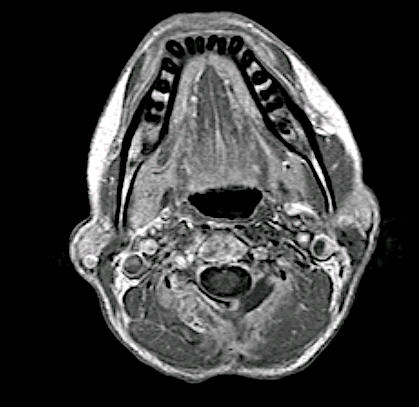

El caso presentaba interés quirúrgico porque el tumor presentaba límites imprecisos (extracompartimental), parecía estar en relación con arteria vertebral dominante y comprimía el saco dural. Se realizó un abordaje posterior para exéresis macroscópica completa. La arteria vertebral se disecó perfectamente al no estar englobada en la masa.

Control postoperatorio. Se resecó la hemilámina izq, artrectomía C3-C4, transversectomía y pediculectomía C3 izq hasta visualizar raíz C4 y arteria vertebral, que pudo disecarse fácilmente, sin incidencias.